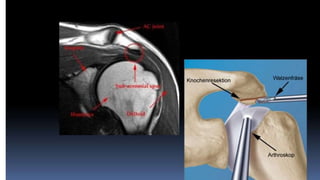

Quirúrgico

Descompresión

Abierta vs Artroscopica

Criterios de Neer

■ Persistencia del dolor por mas de 12 meses con test positivo a la lidocaína

■ Presencia radiológica de un osteofito subacromial

■ Reparación de manguito rotador